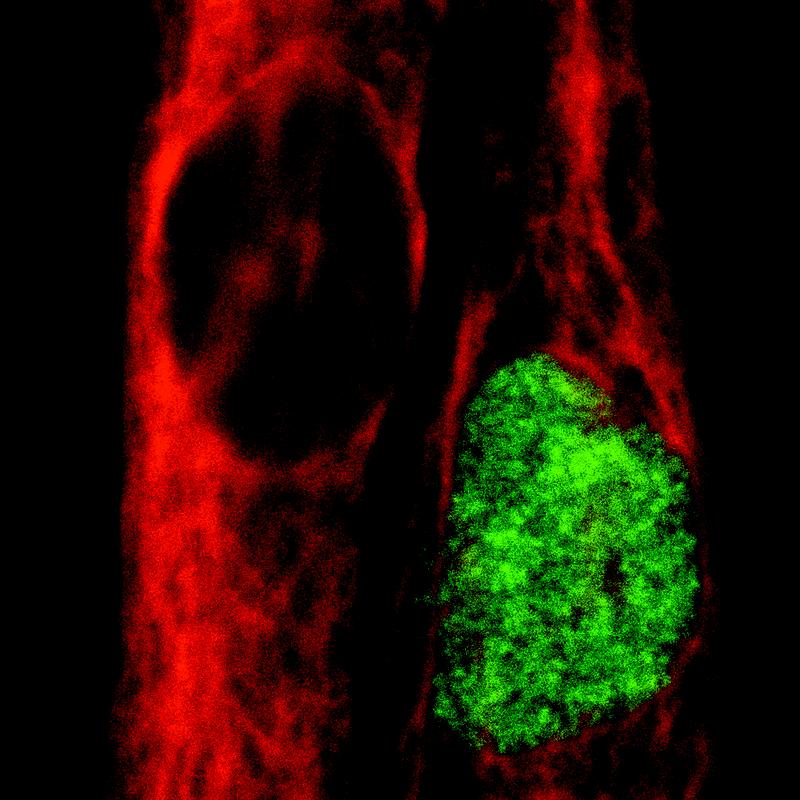

Bitte beachten Sie die neuen Bildunterschriften:

(oberes Bild)

Humane Muskelzelle (rot) und humane Muskelstammzelle (grün).

(Photo: Andreas Marg/ Copyright: ECRC)

Doch mit der Transplantation von Muskelfragmenten allein kann eine genetisch bedingte Muskelerkrankung nicht erfolgreich behandelt werden. Prof. Spuler: „Die Idee ist deshalb, die Satellitenzellen zusätzlich mit einem gesunden Gen zu bestücken, das den Gendefekt repariert, und sie dann mit Hilfe eines nicht-viralen Gentaxis in die zu behandelnden Muskeln einzubringen“. Dass das im Prinzip geht, haben Prof. Spuler und ihre Mitarbeiter in einem ersten Versuch mit einem „Reporter-Gen“ in der Petrischale gezeigt. Es leuchtet grün, wenn es in die Satellitenzelle eingebracht wurde. Als Gentaxi nutzten sie das Transposon „Dornröschen“ – ein springendes Gen, das seinen Ort im Genom verändern kann. Es wurde vor einigen Jahren von Dr. Zsuzsanna Izsvák (MDC) und Dr. Zoltán Ivics (Paul-Ehrlich-Institut, Frankfurt) entwickelt und gilt als vielversprechendes Vehikel für die Gentherapie.